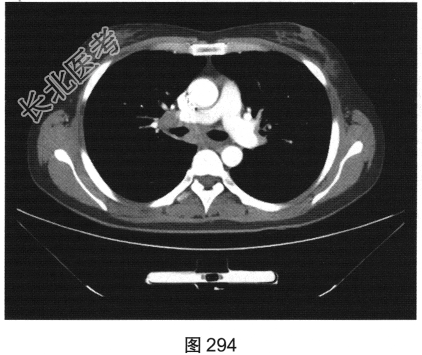

- [材料题] 患者女性,43岁,因“确诊肺低分化腺癌1周”就诊。患者于2014年11月无明显诱因出现咳嗽、咳痰,无胸闷胸痛,无咯血,无发热、乏力、体重减轻等。自服中药治疗,止咳效果尚可。2015年4月22日在山海关人民医院行胸部CT:显示①慢性支气管炎继发感染,建议结合临床及病史考虑;②右侧中间段支气管及中叶支气管壁增厚、管腔狭窄伴右肺中叶阻塞性肺不张,右侧肺门及纵隔多发淋巴结增大,建议增强扫描。后补做增强CT:右肺中叶支气管增厚,管腔狭窄伴阻塞性肺不张,考虑右侧中心型肺癌伴纵隔多发淋巴结增大,建议行支气管镜检查。支气管镜取活检病理:示低分化腺(右肺中叶)癌,建议做免疫组织化学检测,以进一步明确诊断。于北京肿瘤医院行PET/CT检查:①右肺中叶支气管起始部位高代谢结节,符合中心型肺癌表现;右肺中叶部位阻塞性不张,不张肺内高代谢结节,倾向肺内转移;双肺多发转移结节;双锁骨上区、左胸肌间、纵隔及双肺门多发淋巴结转移。②脑部未见明显高代谢征象,建议行增强MRI检查。③双叶甲状腺炎性或非特异性摄取,建议行B超及甲状腺功能检查。患者精神状态良好,体力、食欲、睡眠均正常,体重无明显变化,大便、排尿正常,为进一步检查及治疗,门诊以“肺癌”收入院。2015年5月5日在我院行CT检查,如图288~图295所示。